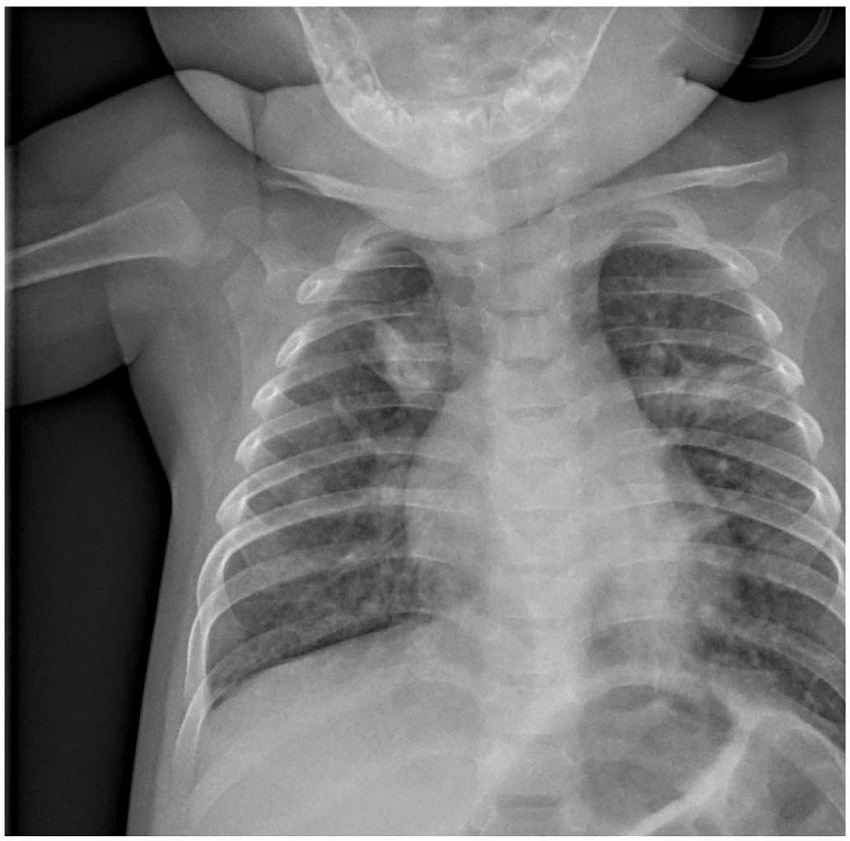

A su llegada a urgencias, presentaba hipoxemia con saturaciones basales en torno al 85%. Se realizó una radiografía de tórax, en la que se apreciaron consolidaciones segmentarias bilaterales en lóbulos superiores y retrocardíaca, sugestivos de infección por COVID-19 (figura 1). Los reactantes de fase aguda en la analítica no estaban elevados (leucocitos 7,28 x 103, proteína C reactiva 3,4 mg/L, D-dímero 450 ng/mL). Se pautaron broncodilatadores (salbutamol), hidroxicloroquina, corticoterapia (estilsona) y antibioterapia (amoxicilina-clavulánico), y la paciente remontó hasta una saturación de oxígeno (SatO2) del 100% con oxígeno a 3 L. Se realiza una PCR para SARS-CoV-2 en la orofaringe, que resultó positiva.